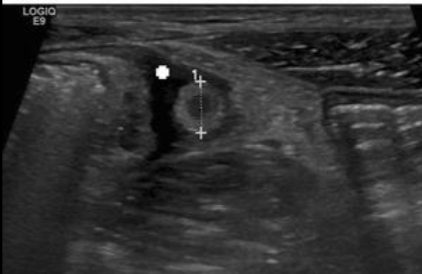

10

Q

A

11

De frente obstrucción luminal